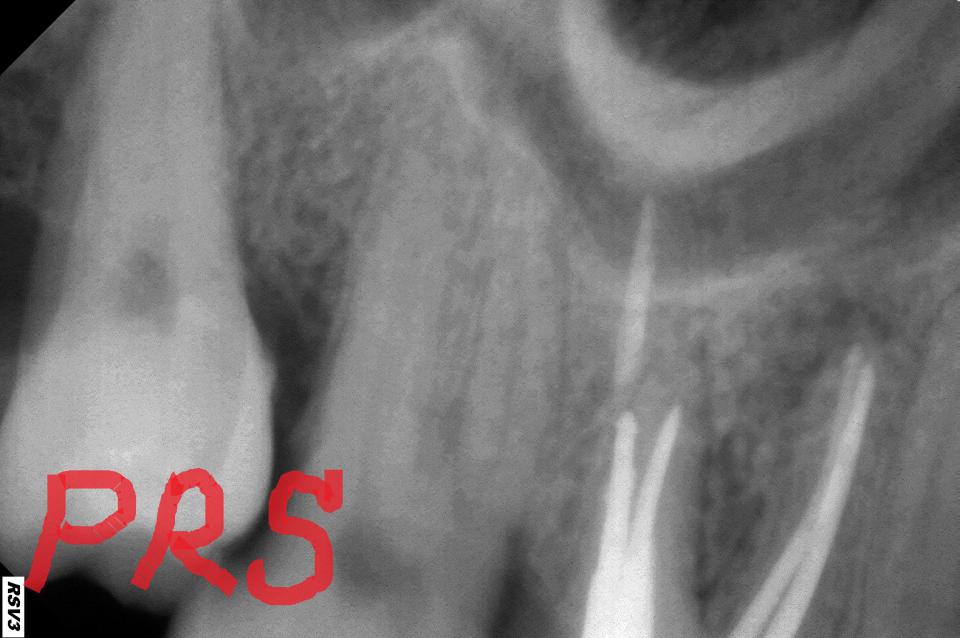

paraschyk1 Опубликовано 8 августа, 2013 Автор Опубликовано 8 августа, 2013 Ой AT0N,беги. Беги к другому спецу. 1.Если зуб со всех сторон разрушен и во множестве пломб,плюс уже депульпирован (удалены нервы)-это коронка. 2.За 30гр будет скорее всего самый дешевый анкерный (металлический штифт),потому как стекловолокныый штифт (СВШ) по 15-60гр/штука в закупке. Большая половина докторов,к тому же,не умеет правильно фиксировать СВШ. В таких руках лучше будет работать анкерный. 3.Конструкция эта (хим.ком + мет.штифт) гуано,так как долго держать герметизм не будет и гнить начнет под ней. Фото.пол+мет.штифт получшее. 4.Врач который делает такие сравнения и выводы о пломбировочных мат-лах,пардон,но профан. Даже сами фотополим. в зависимости от своей наполненности разной прочности. Предложила она тебе хим.комп потому,что ей проще им зашпаклевать зуб,чем лепить из фото. Исходя из изречений лечащего тебя врача,назрел вопрос о адекватности пломбировки корневых каналов (к/к). Если снимок у тебя можешь сравнить с ниже представленными. В 6х и 7х зубах в основном (70-80%) 4ре к/к,бывает и 5ть. На снимках как раз можешь видеть такие случаи. Но если твой врач хотя бы три канала,сравнительно так,запломбировала можно что-то думать дальше. Если нет,айда по новой. На твоем месте я бы восстанавливал зуб коронкой.